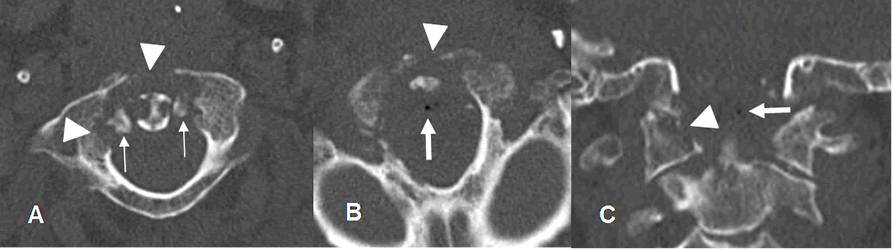

Fig 143 B. Absceso epidural.

A y B: TAC axial. C: TAC reconstrucción coronal. Igual paciente anterior. Mala evolución clínica, con fiebre y sepsis. En el TAC de control se encuentra osteolisis del arco anterior y el lado derecho de C1 y la odontoides, por osteomielitis. (Puntas de flecha). Hay fragmentos óseos libres dentro del canal. (Flechas delgadas). Adicionalmente existen burbujas de aire dentro del canal, por la formación de absceso. (Flechas gruesas).